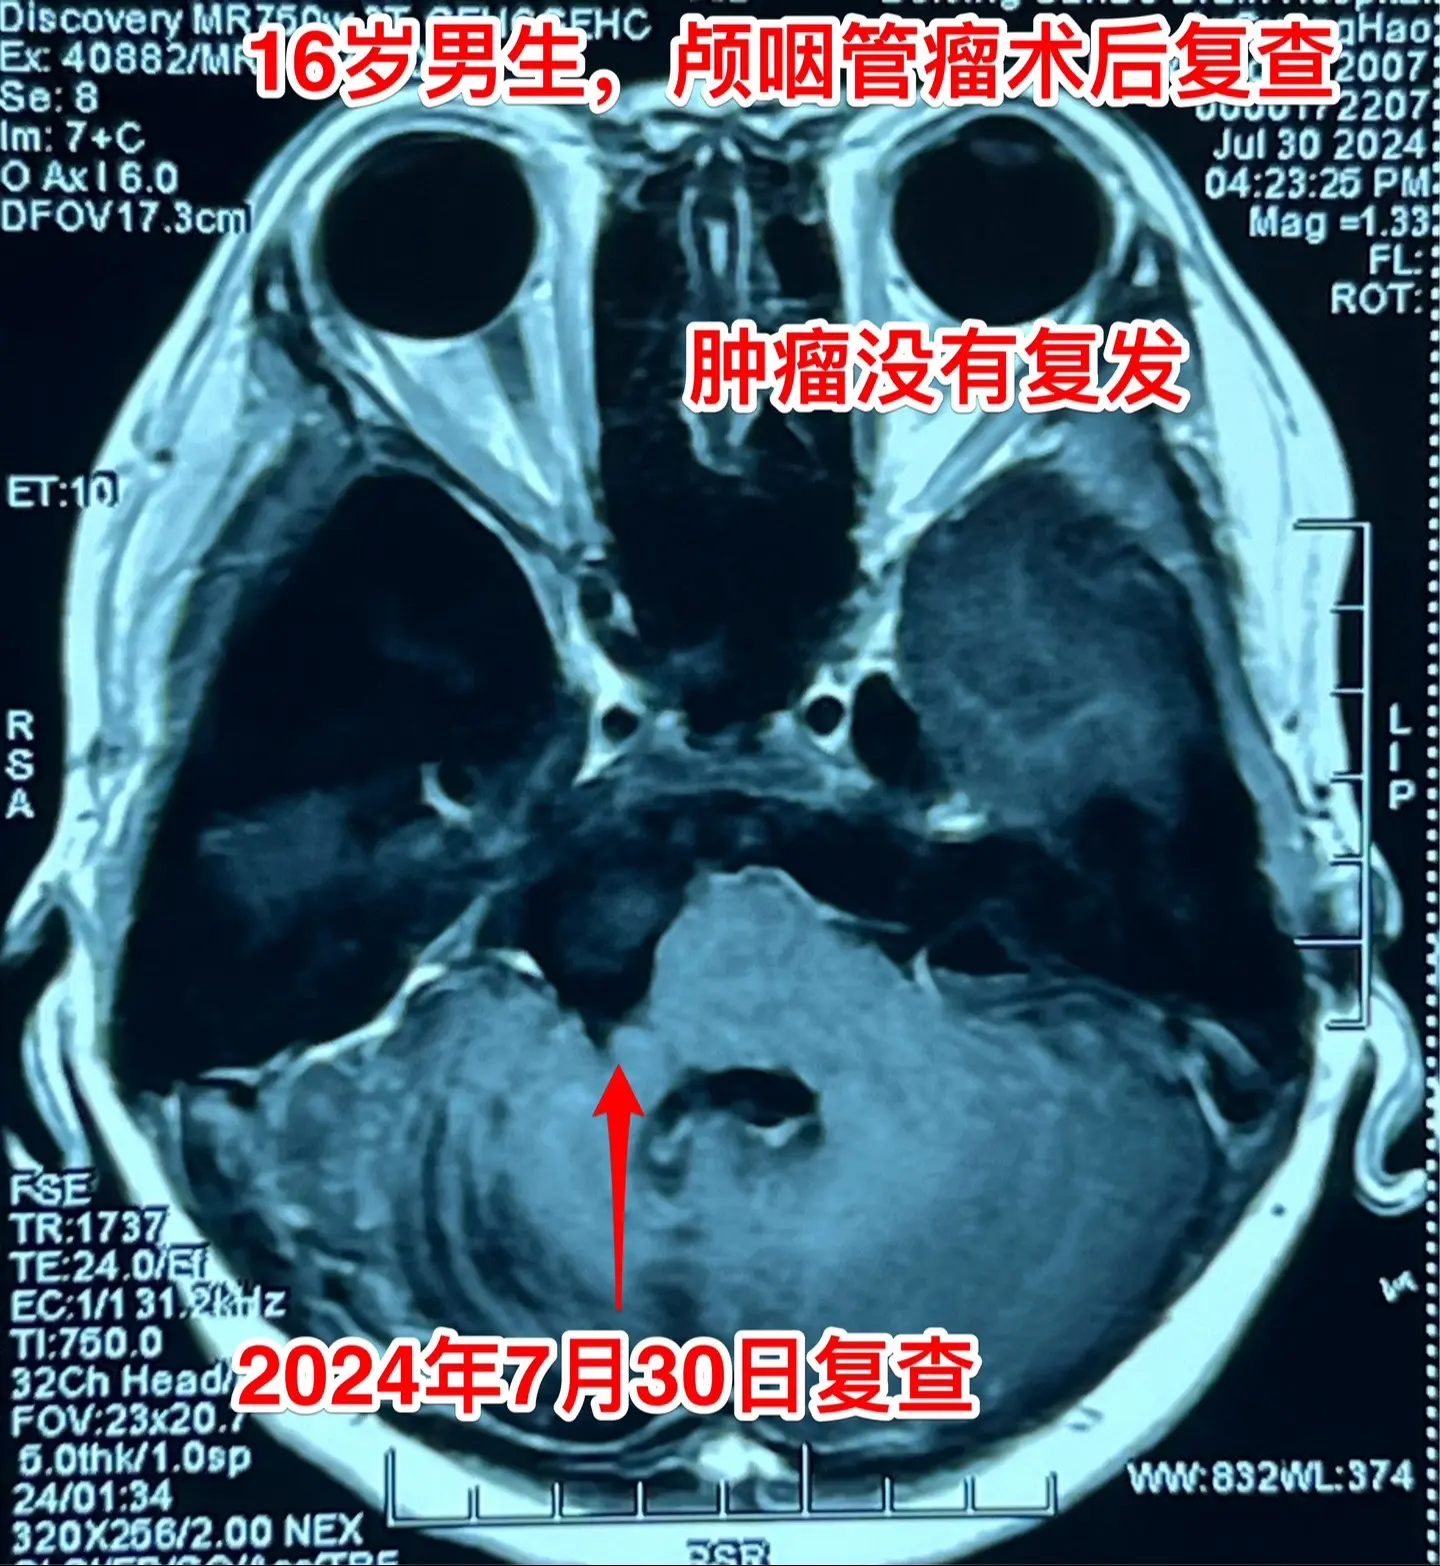

颅咽管瘤复发导致听力下降眼睑下垂。2024年7月30日 16岁男孩子颅...

2024-08-04 23:43